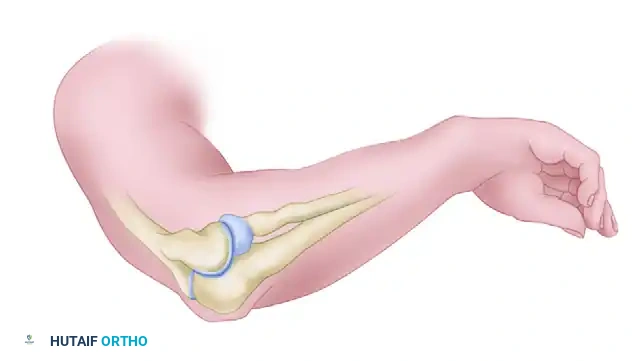

The elbow joint is highly susceptible to post-traumatic stiffness due to its highly congruent osseous anatomy, complex capsuloligamentous structures, and profound propensity for robust fibroblastic responses following injury. A normal elbow possesses a range of motion (ROM) from 0 degrees of extension to 140 degrees of flexion, with 70 to 80 degrees of both pronation and supination. However, the functional arc of motion—as classically described by Morrey—requires only 30 to 130 degrees of flexion and 50 degrees of pronation and supination to perform most activities of daily living (ADLs).

Anterior and Posterior Release of Elbow Contracture (Morrey Technique)

The extensile lateral approach, popularized by Morrey, is a workhorse technique for addressing severe elbow contractures. It allows simultaneous access to the anterior and posterior compartments while preserving the critical medial structures, provided the dissection respects the anatomic boundaries.

The Extensile Lateral (Kocher) Approach

The surgical exposure begins with an extensile modification of the classic Kocher approach, designed to provide panoramic access to the lateral column of the distal humerus and the radiocapitellar joint.